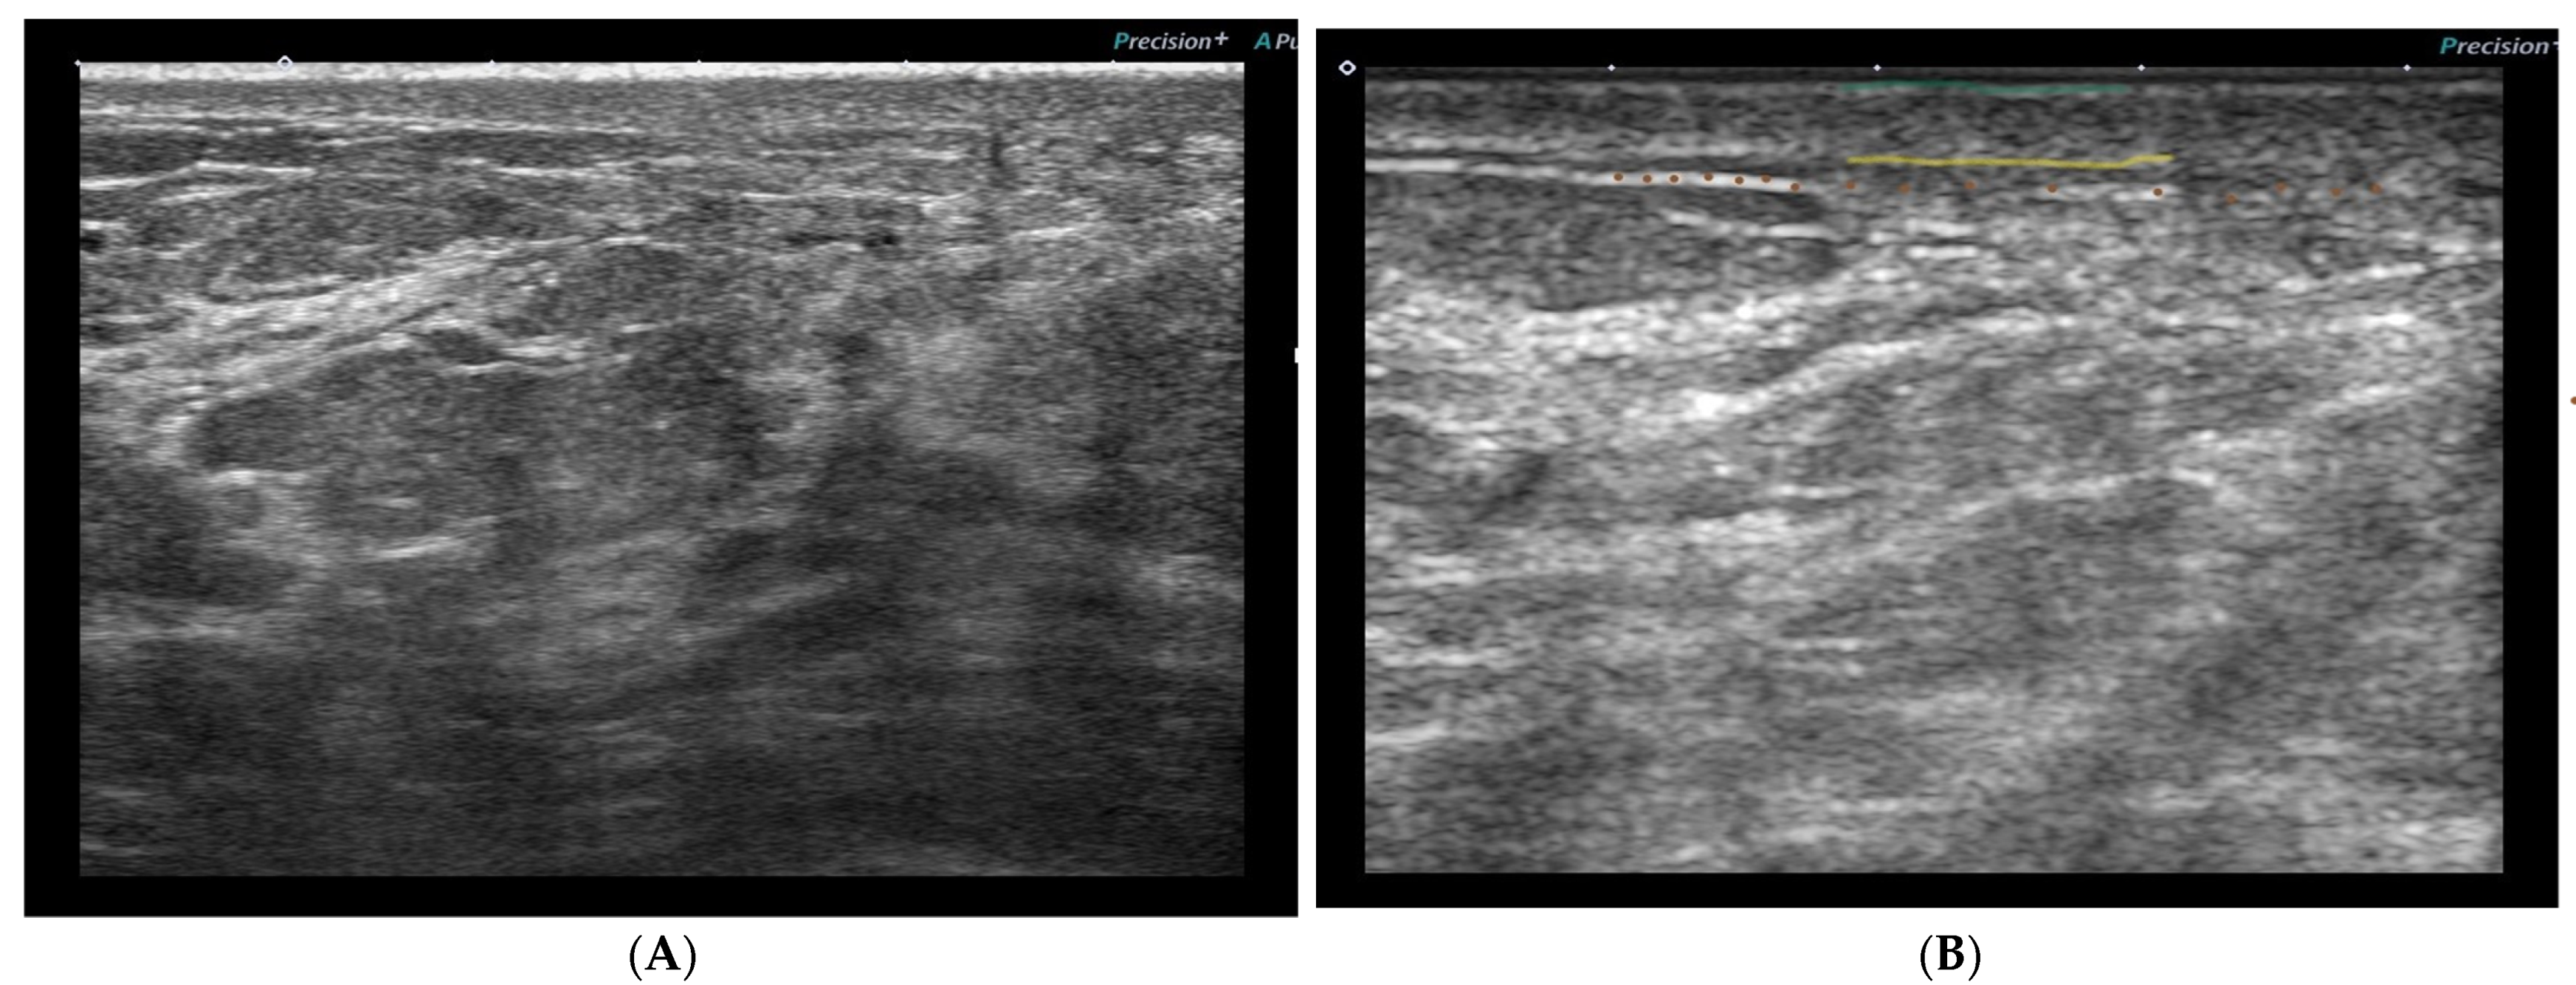

3.3. Ultrasound Protocol

3.4. US Skin Parameters and Locations of the Measurements

3.5. Ultrasonographic Skin Toxicity Changes